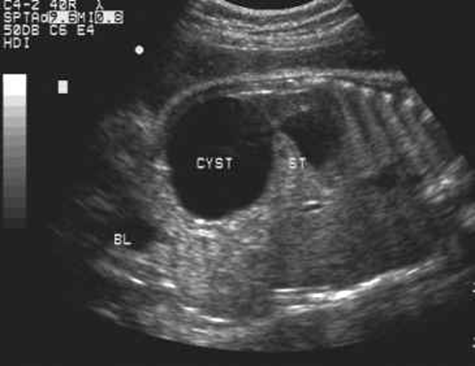

Ovarian Cyst